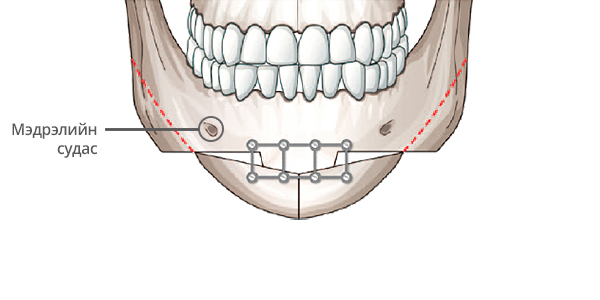

Step 2

Нүүрний уртад тааруулж ясны хэсгийг зүсэж авна.